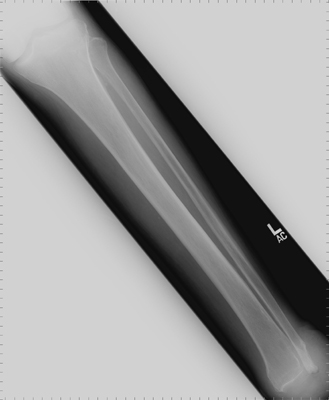

and thus non-cosmetically pleasing prosthesis. The level of

the amputation in generally at the distal tibia and fibula 0.6cm proximal to the periphery

of the ankle joint and passing through the dome of the ankle centrally. In the past,

The MRI images below demonstrate the level of the Symes amputation along with bony and

soft tissue changes. Note the thick heel pad forming the majority of the distal

stump: the principle advantage of this procedure due to the more effective weight bearing.